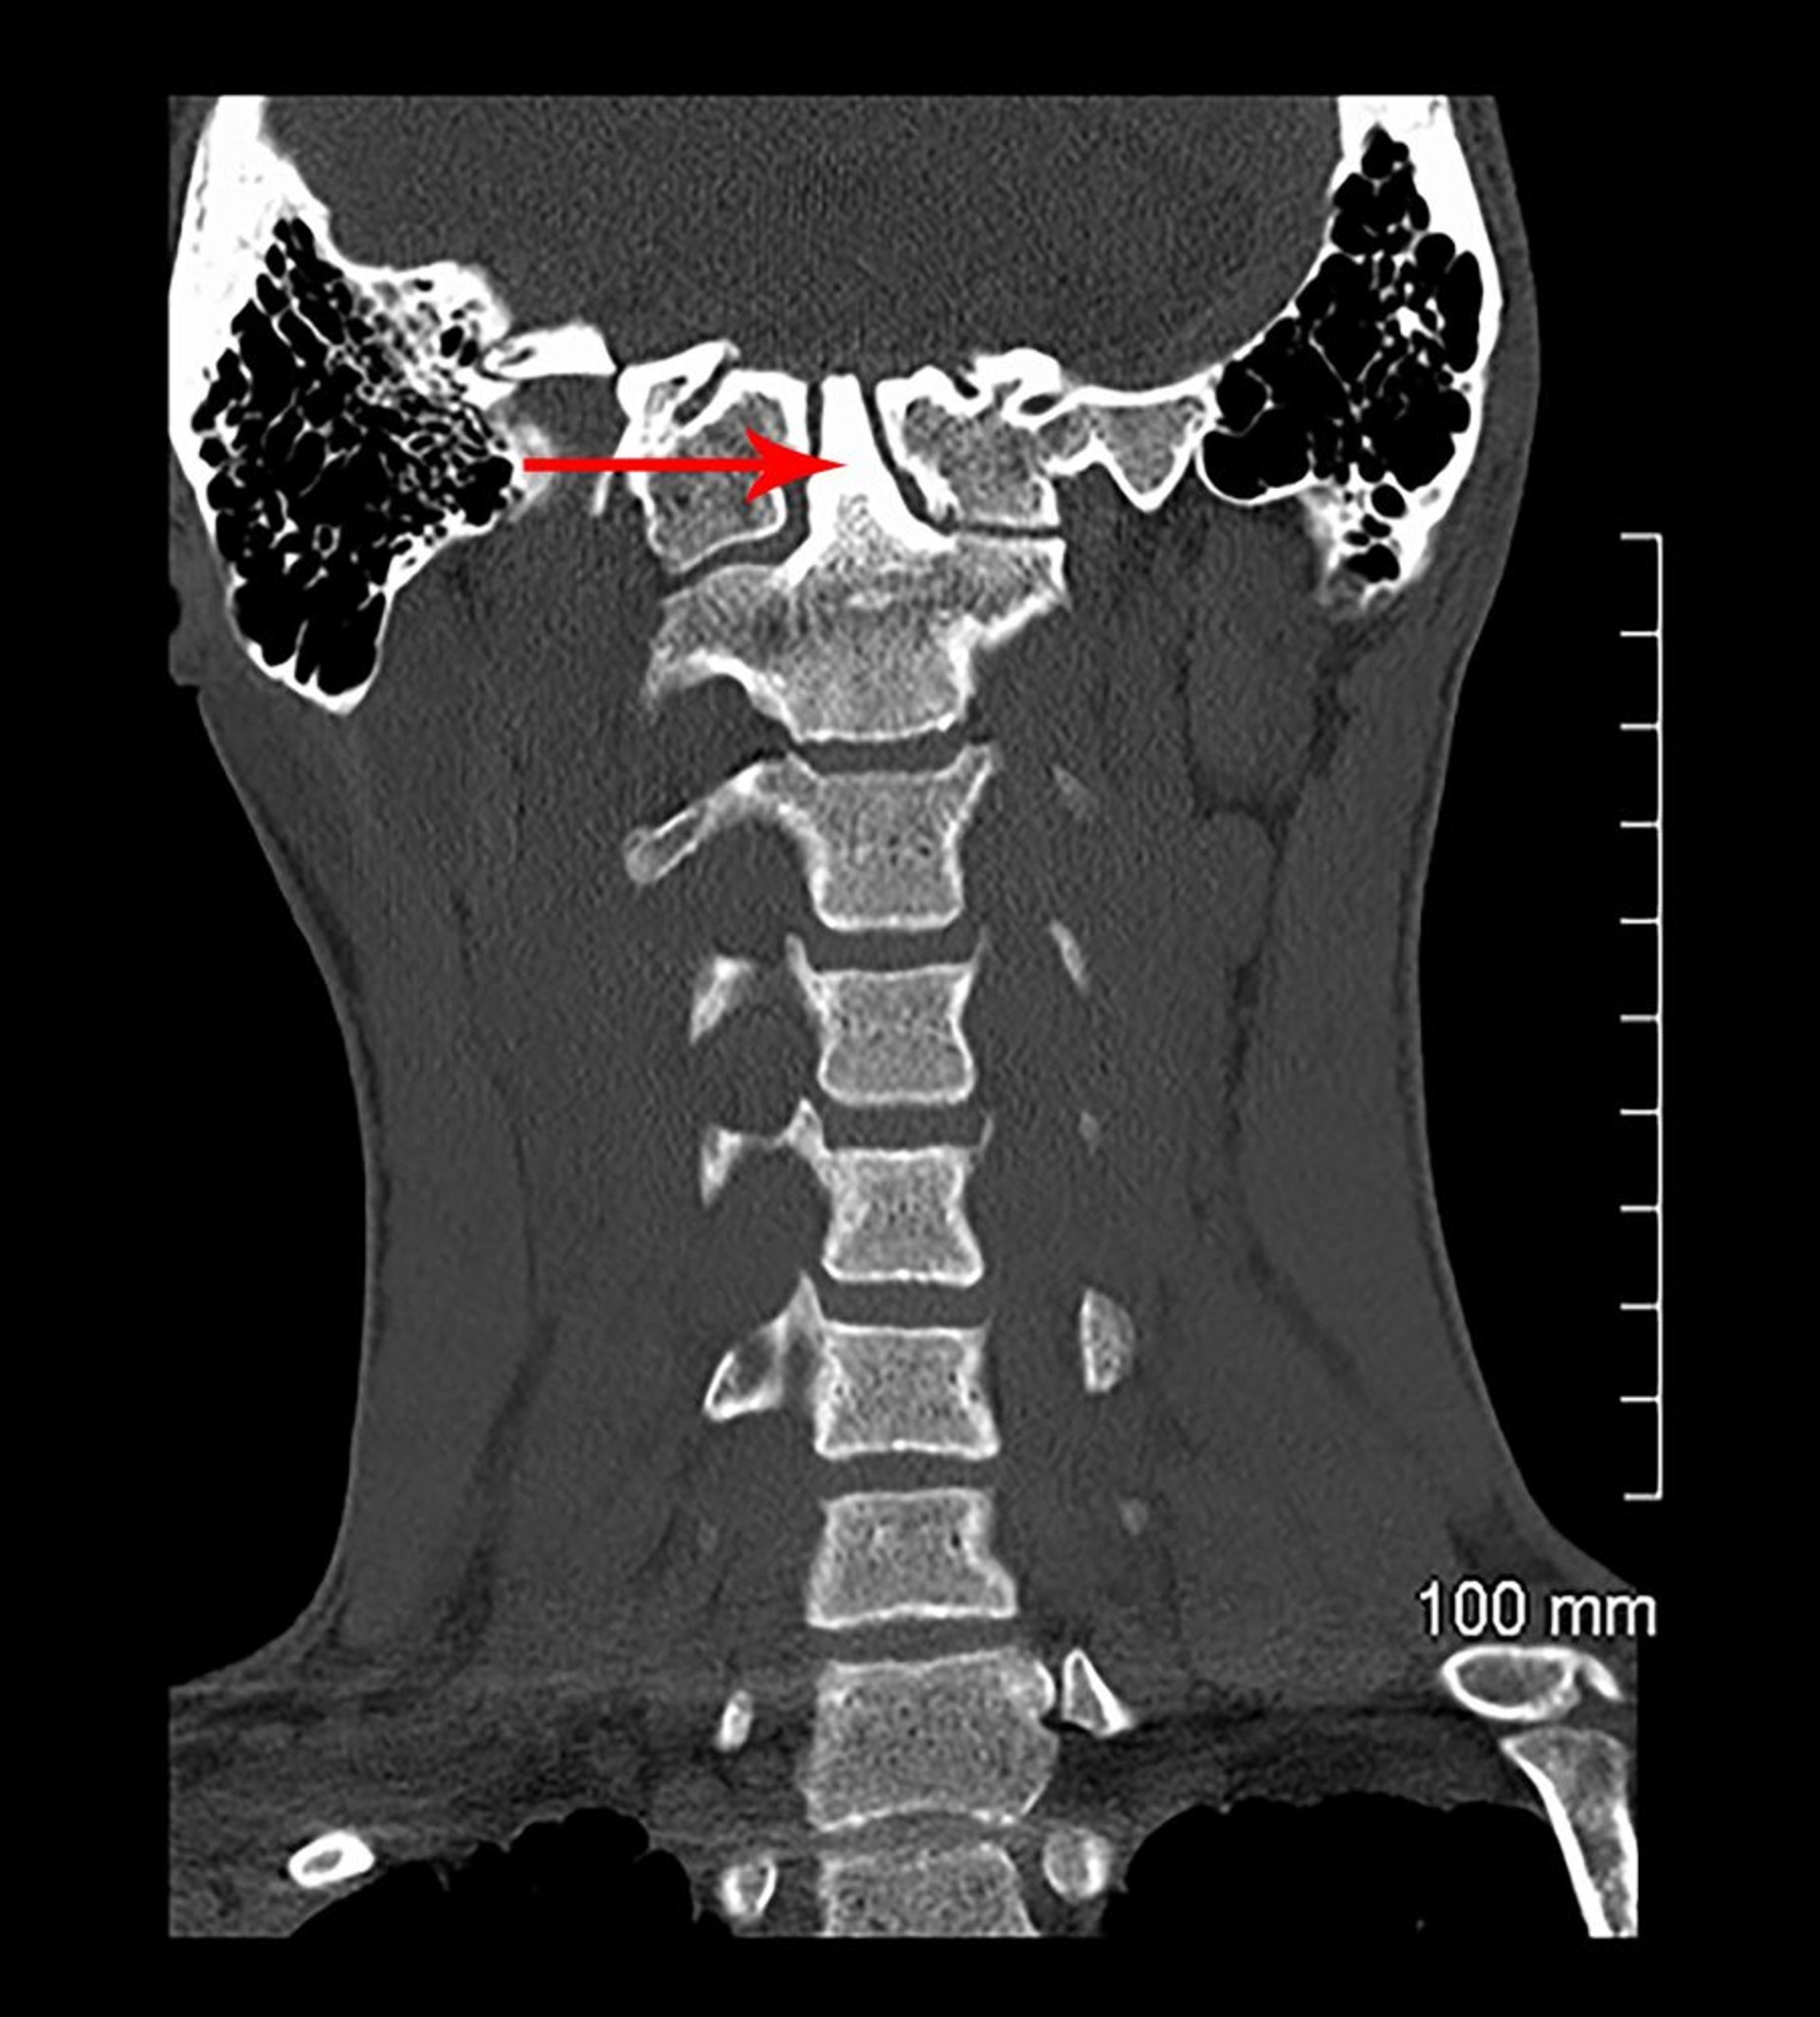

Invaginación basilar y asimilación congénita (TC)

En esta vista coronal de una tomografía computarizada, se observa la fusión de C1 con la base del cráneo (congénita). La apófisis odontoides (indicado por una flecha) se extiende hacia la base del cráneo (invaginación basilar).